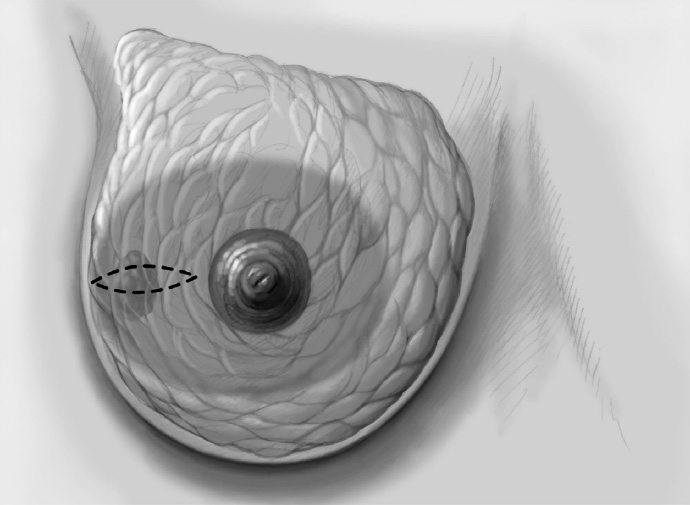

The skin is incised over the tumor region as far as possible (depending on surgeon, tumor size, tumor location, and subsequent treatment). A radial incision may be useful for tumors located in the lower quadrants or directly in the axillary tail of the breast. If the tumor is just beneath the skin, an island of skin over the tumor should be resected also. This can be achieved with both an elliptical semicircular incision and a radial incision. Another form is a purely periareolar incision when the tumor is in a relatively central position (see illustrations below).

The basic decision on whether to use a complex oncoplastic technique is made when the skin is marked preoperatively, with the patient standing or sitting upright. Many surgeons successfully combine the B-plasty incision with periareolar de-epithelialization and excision of a straight or curved ellipse of peripheral skin (Chapter 1.3). When marking the periareolar deepithelialization pattern, an eccentric incision may be necessary to adjust the repositioning of the nipple–areola complex to the anticipated volume displacement.

To cover the defect, the glandular lobes are mobilized from the adjacent parenchyma after subcutaneous dissection. The principle of intramammary lobe creation is to mobilize large parts of the breast (> 25%) either relative to the skin or relative to the pectoralis muscle. This “liberation” of the breast from one of its two planes of fixation allows adequate dissection and rotation of sufficient breast tissue. The Y-flap and rotation flap shown in Chapter 3.2.1 are examples of intramammary dissection.